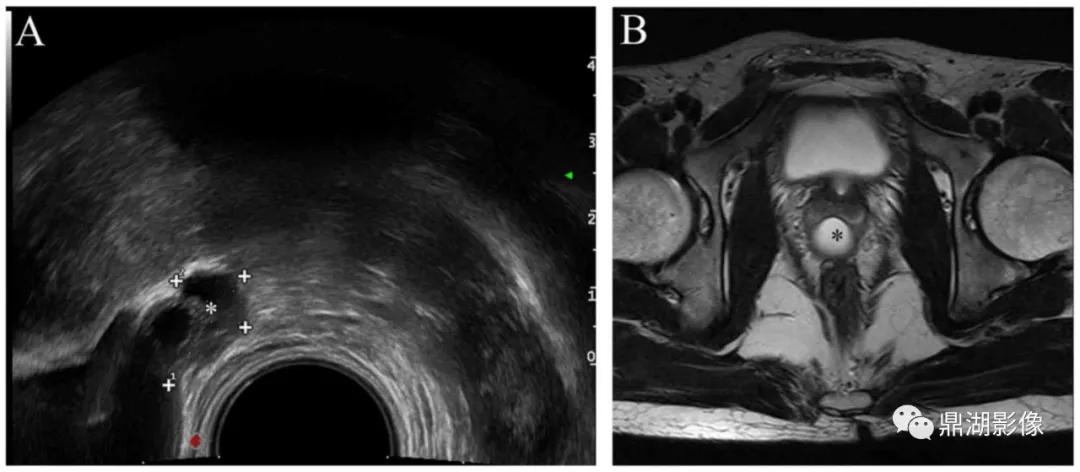

超声:膀胱后壁后上方宫颈前唇及阴道上段区域囊性占位病变,性质待查。

病例二